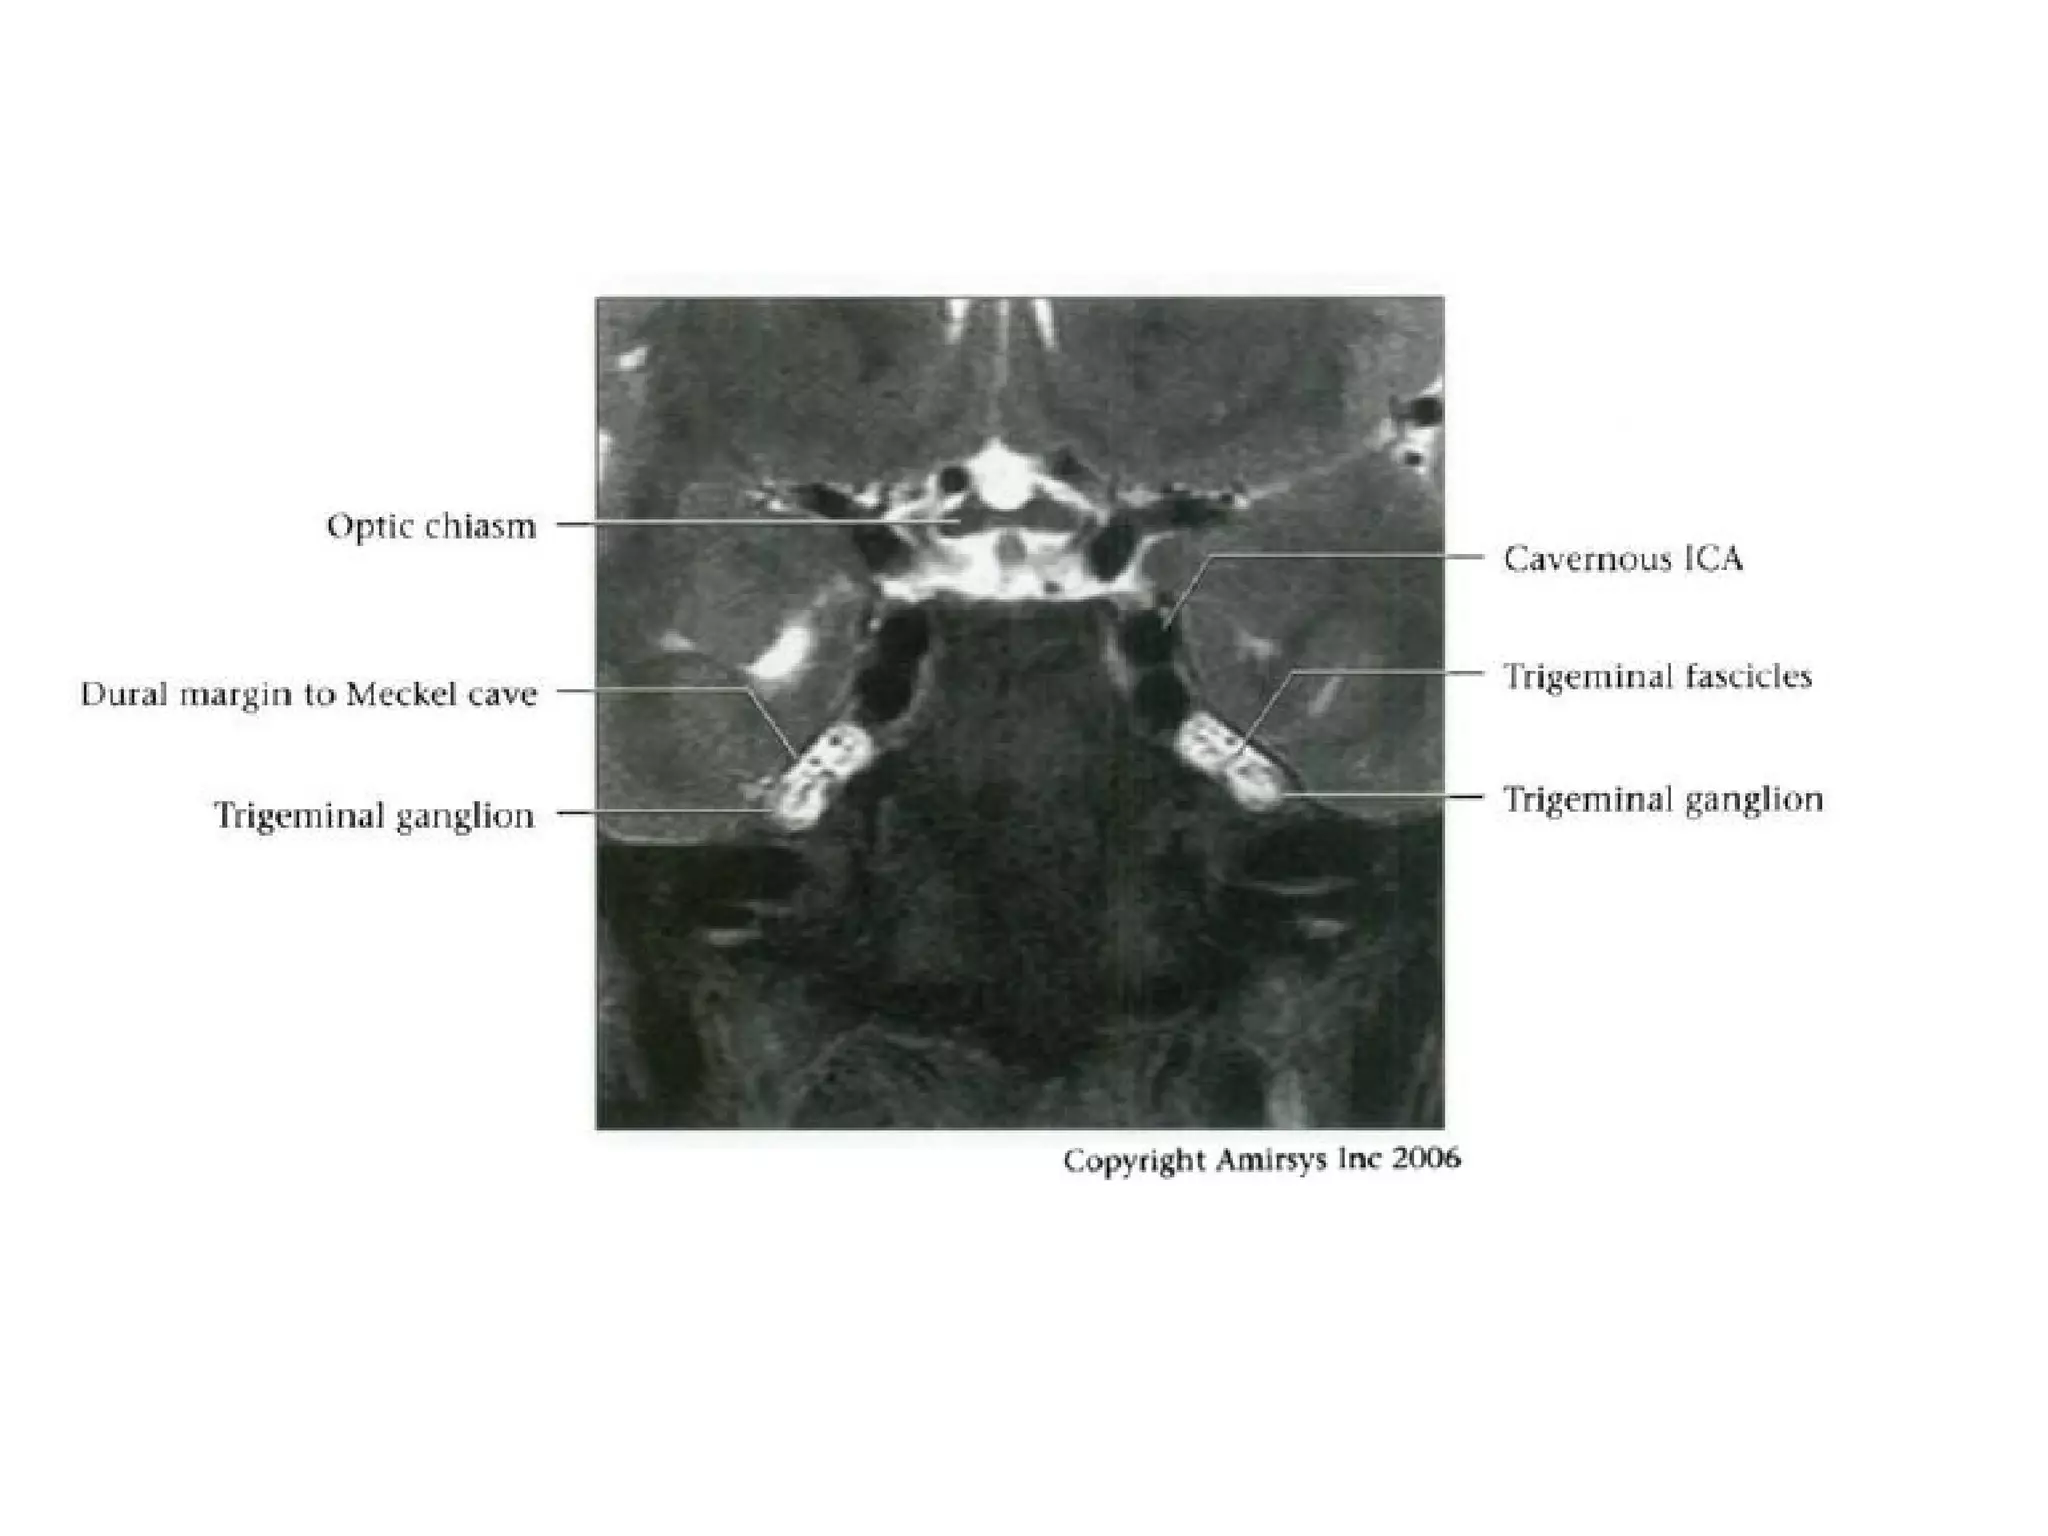

Cranial Nerve V:

The Trigeminal Nerve

• The trigeminal nerve is the largest cranial nerve.

• It is composed of a large sensory root that

runs medial to a smaller motor root.

• The roots emerge from the lateral midpons and

travel anteriorly through the prepontine cistern

and the porus trigeminus to the Meckel

(trigeminal) cave, a CSF-containing pouch in the

middle cranial fossa.

• In the Meckel cave, the nerve forms a meshlike web that

can be visualized only with high-resolution imaging.

• Along the anterior aspect of the cavity, the trigeminal

nerve forms the trigeminal (gasserian) ganglion before

splitting into three subdivisions.

• The ophthalmic (V1) and maxillary (V2) divisions of the

nerve move medially into the cavernous sinus and exit

the skull through the superior orbital fissure and foramen

rotundum, respectively.

• The mandibular division (V3), which includes the motor

branches, exits the skull inferiorly through the foramen

ovale.

RadioGraphics 2009; 29:1045–1055